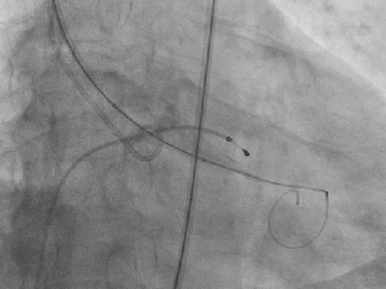

病例2:高龄、长期心功能不全

患者为70岁男性。因劳力性气喘无法活动入院。

术前检查:

超声提示主动脉瓣重度狭窄合并中度关闭不全,二尖瓣中等量反流,三尖瓣少量反流。

最终影像